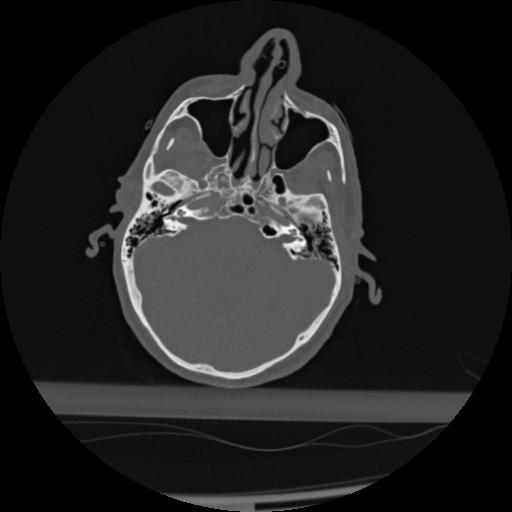

22 ANGIO,CE,Vol,0.5,ANGIO,,